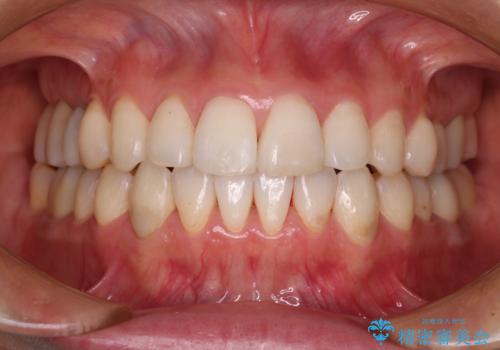

矯正治療後には期にある銀歯を全てセラミッククラウンなどで補綴治療することとしました。

インビザライン・ライトによる矯正治療であったので、時間をかけずに治療を終えることができました。

口を開ける度に目立っていた銀歯もセラミックで自然な口元の印象となりました。